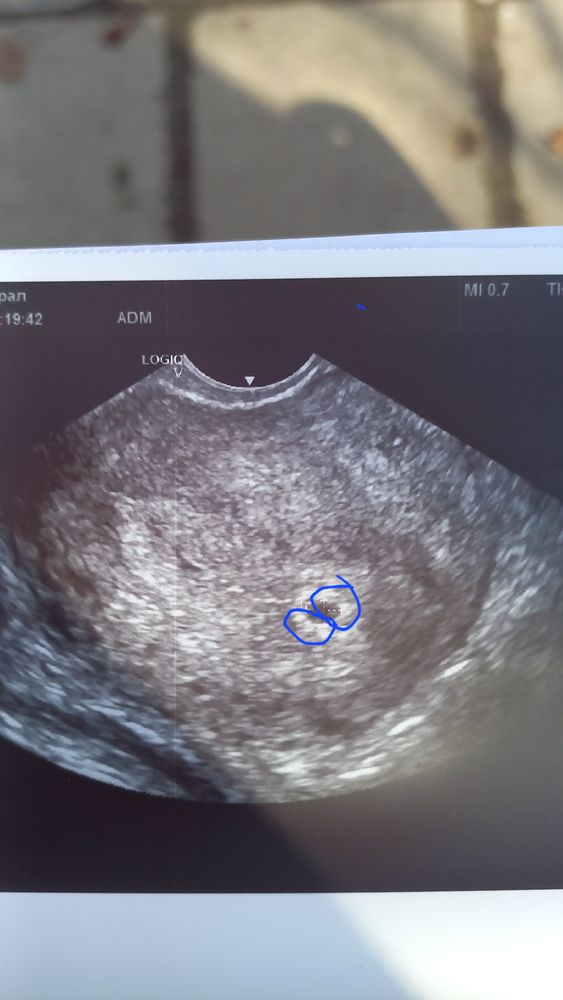

Беременность двойней???

Всем привет,может ли быть двойня?Сама из двойни по счету это 3 беременность.

По этому узи пока ничего не ясно. Эмбрионов не видно.

Зуля, тогда отметтьте, я не вижу 🤷♀️ вижу только пунктир, который показывает размер плодного яйца. 👀

Зуля, вы не обижайтесь,но я ничего не вижу. Вижу плодное яйцо и все. А какой у вас срок по месячным?

Надежда, я наверное много читала про многоплодную и накрутила 😁😁

5.4

А по сроку беременности 4.4

Зуля, очень рано еще для визуализации эмбрионов) подождите дней 10, и уже можно будет что-то разглядеть. Ну и вам в заключении должны были указать наличие эмбриона, 1 или 2 если бы их уже видно было